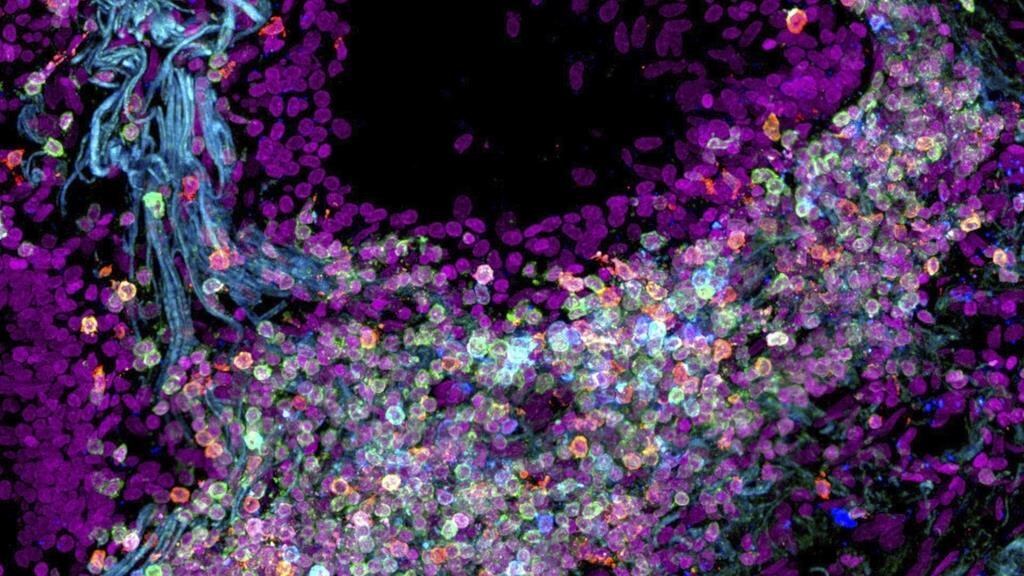

Des chercheurs ont créé une première carte de certaines des 37,2 mille milliards de cellules du corps humain.

Les scientifiques se sont concentrés sur certains organes, en traçant le rôle des cellules de la bouche, de l'estomac et des intestins, ainsi que des cellules qui guident le développement des os et des articulations.

Ils ont également exploré les groupes de cellules en tissus, leur emplacement dans le corps et leur évolution au fil du temps.

La carte cellulaire actuelle ne répertorie pas seulement les nombreux types de cellules humaines, mais elle montre également les relations des cellules entre elles, a indiqué le docteur Timothy Chan, un spécialiste du cancer à la Cleveland Clinic.